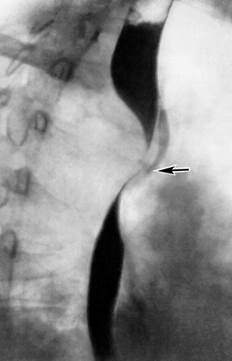

Больной доставлен в приемный покой, попал в ДТП. Получил сильный удар в грудь рулевым колесом. При поступлении на вопросы отвечает. Жалобы на сильные боли в левой половине грудной клетки. Состояние средней степени. Кожа и видимые слизистые бледно-розовые. АД – 100/70 мм рт, ст., пульс 95 в мин. Левая половина грудной клетки несколько отстает при дыхании. Над легкими везикулярное дыхание, хрипов нет. Слева в нижних отделах незначительное ослабление. Пальпаторно болезненность по задней поверхности грудной клетки слева. В проекции угла лопатки. На ренгене:  Диагноз? //

Диагноз? //

Тупая травма грудной клетки. Перелом 6-7 ребер слева со смещением. Пневмоторакс слева. Травматический шок 1 степени//

Тупая травма грудной клетки. Перелом 6-7 ребер слева без смещениея. Пневмоторакс слева. Травматический шок 2 степени//

+Тупая травма грудной клетки. Перелом 6-7 ребер слева со смещением. Травматический шок 1 степени//

Тупая травма грудной клетки. Перелом 6-7 ребер слева со смещением. Травматический шок 2 степени//

Тупая травма грудной клетки. Перелом 6-7 ребер слева без смещениея. Травматический шок 1 степени